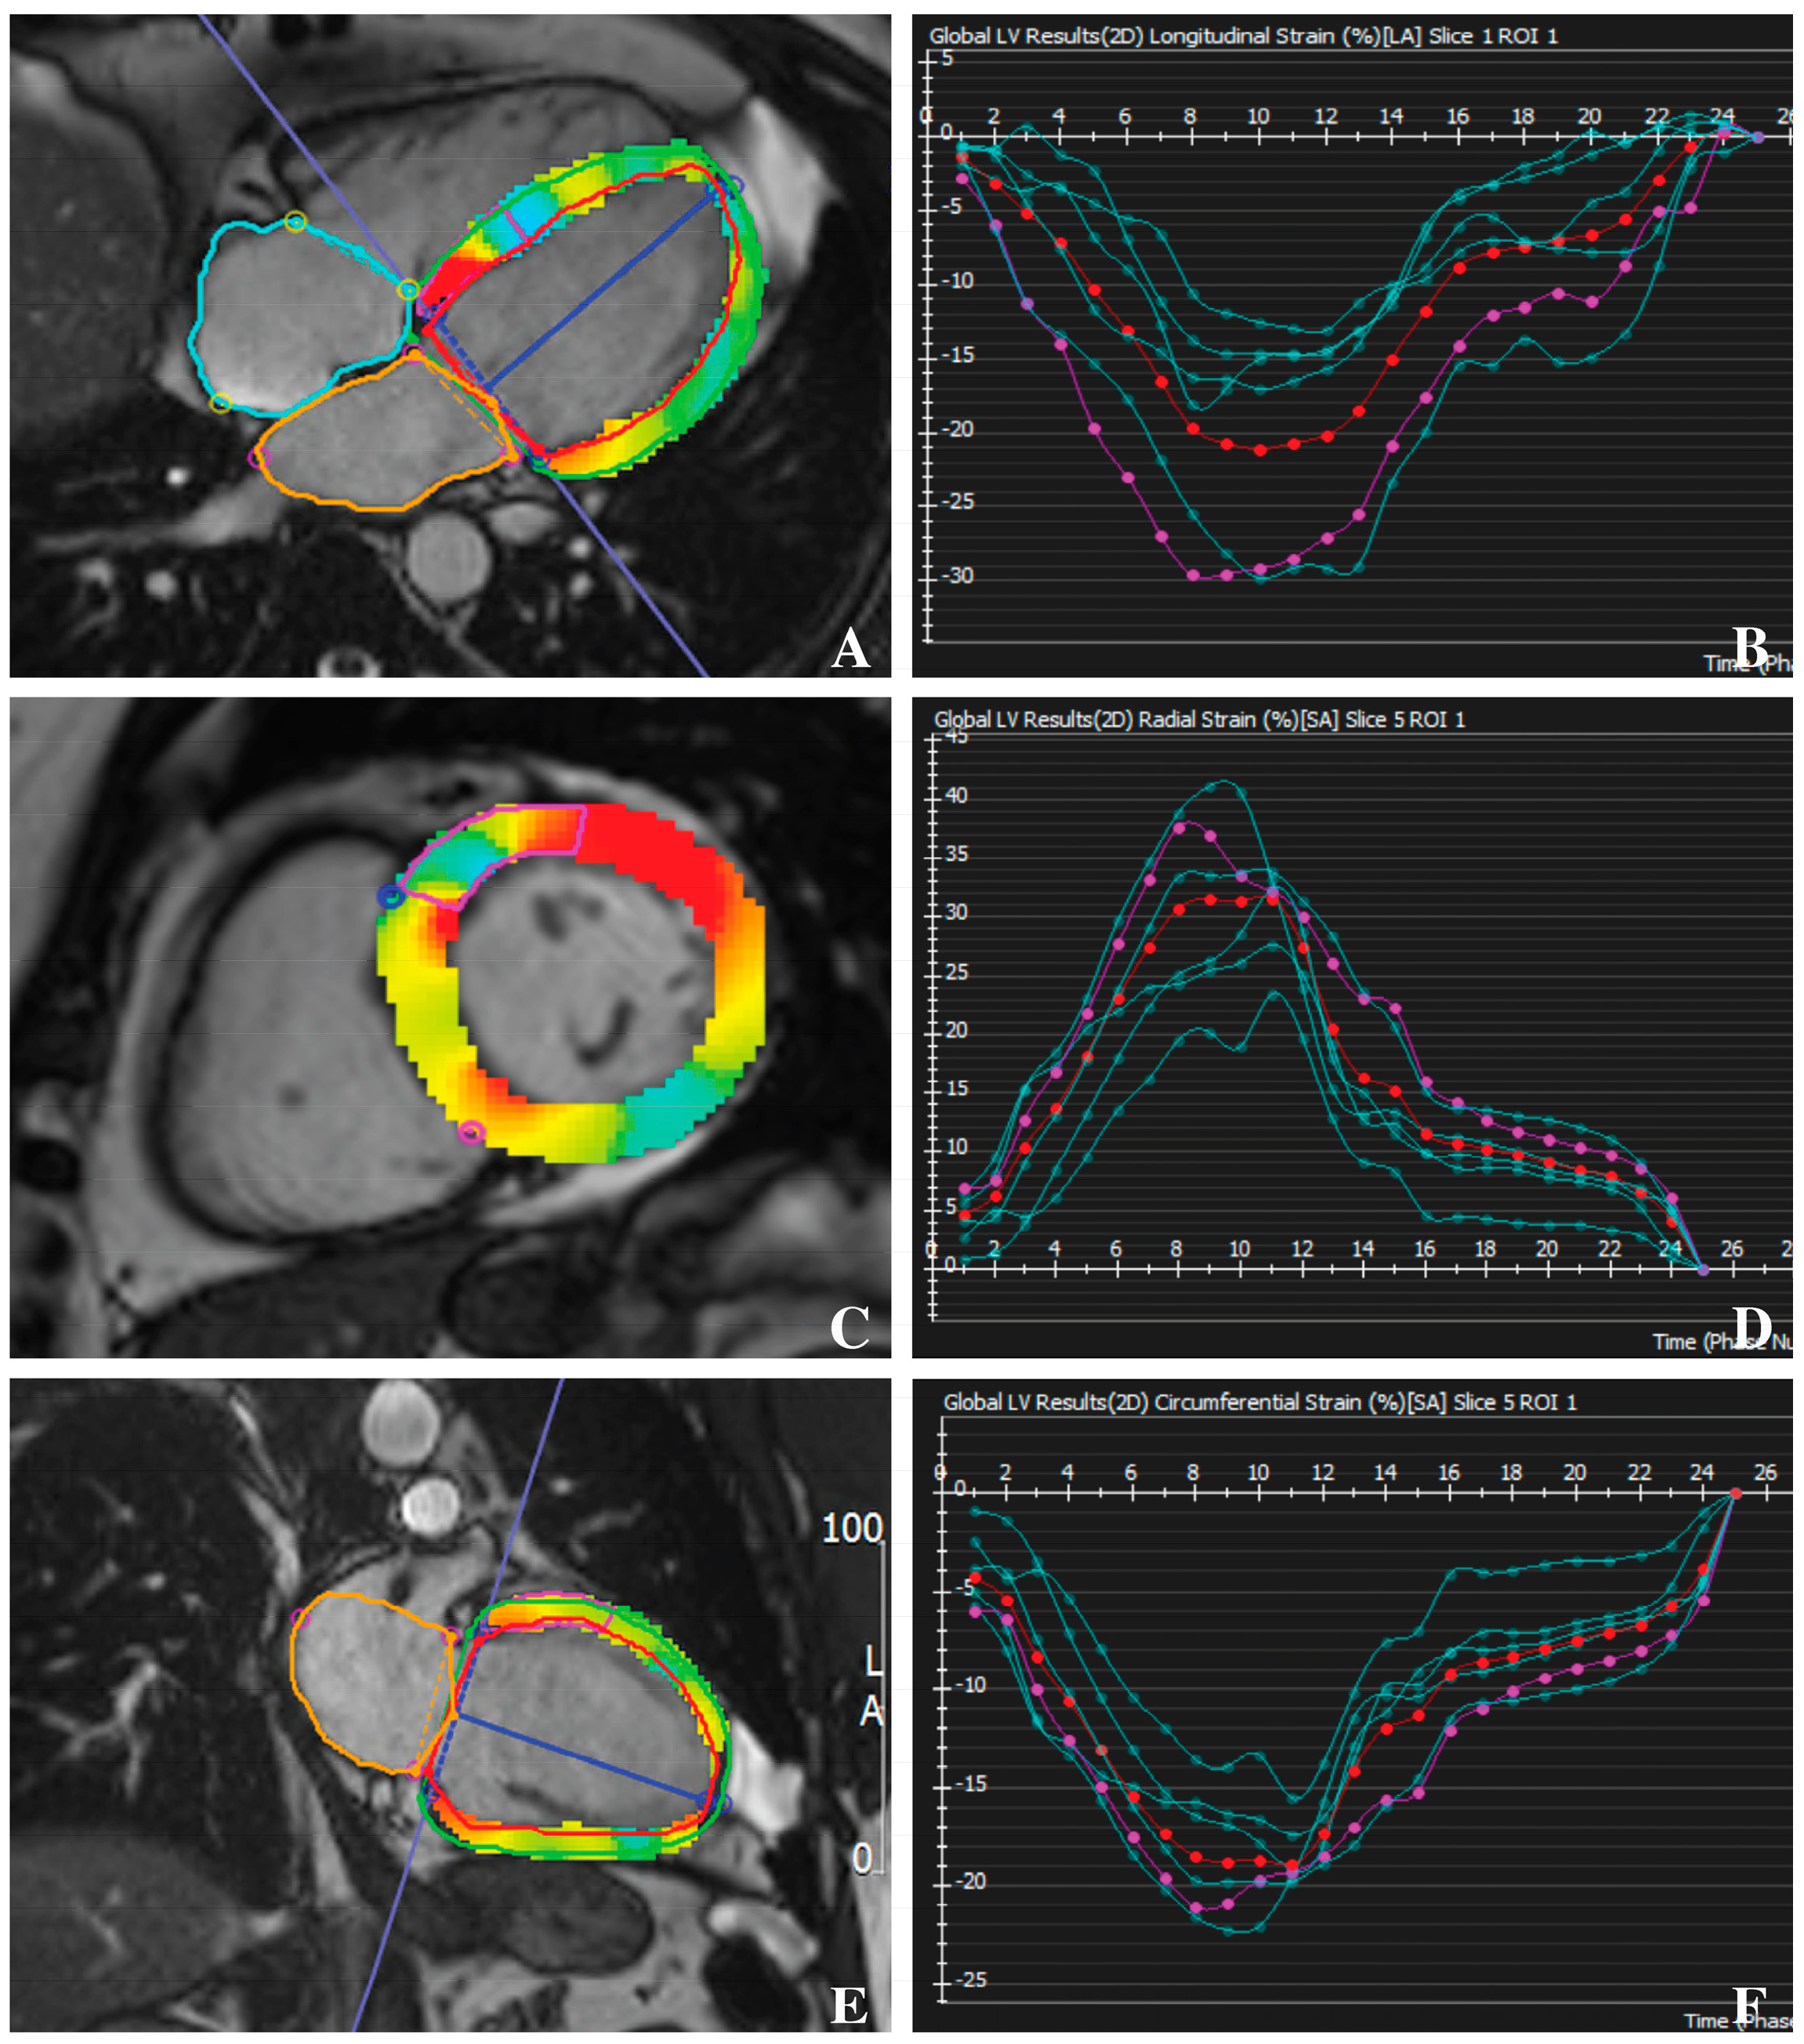

2.3. Feature-Tracking CMR